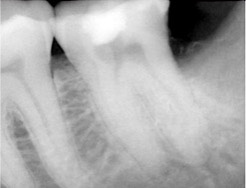

A 25 years old female came with the complaint of pain and sensitivity in mandibular left first molar (Figure 2). After clinical and radiographic examination and endodontic therapy was advised.  After anaesthetizing the tooth, access preparation was done and canal orifices were located with DG 16 endodontic explorer. Initial negotiation of the root canals was performed with K-file # 10. Thereafter GenEndo files were used in a sequential order as per the manufacturer’s instructions.  CF file (Coronal Flare file) was first used to perform the coronal flare. Thereafter, 10 K-file was used to measure the working length using an electronic apex locator (Canalpro, Coltene). Thereafter, GPF was used up to the WL in order to make a smooth glide path for the larger files to follow. Subsequently, the PF and UFI were used in the sequential order up to the WL to complete the preparation. Warm 5 % sodium hypochlorite (warmed using Syringe warmer, Coltene) was used throughout the procedure as the irrigant. Calcium hydroxide was given as intracanal medicament. In the next appointment, as the patient was asymptomatic,  master cone fit radiograph was taken  using corresponding GP Points (GenENDO) which  revealed proper fitting of respective GP cones. Canals were dried with paper points and obturation done by using single cones of corresponding taper and size as MAF, using Gutta Flow Bioseal sealer (Coltene). The fine and curvy mesial canals and two distinct distal canals in this tooth can be easily appreciated (Figure 3).

Figure 3 Post-operative radiograph showing fine mesial canals and two distinctive distal canals.